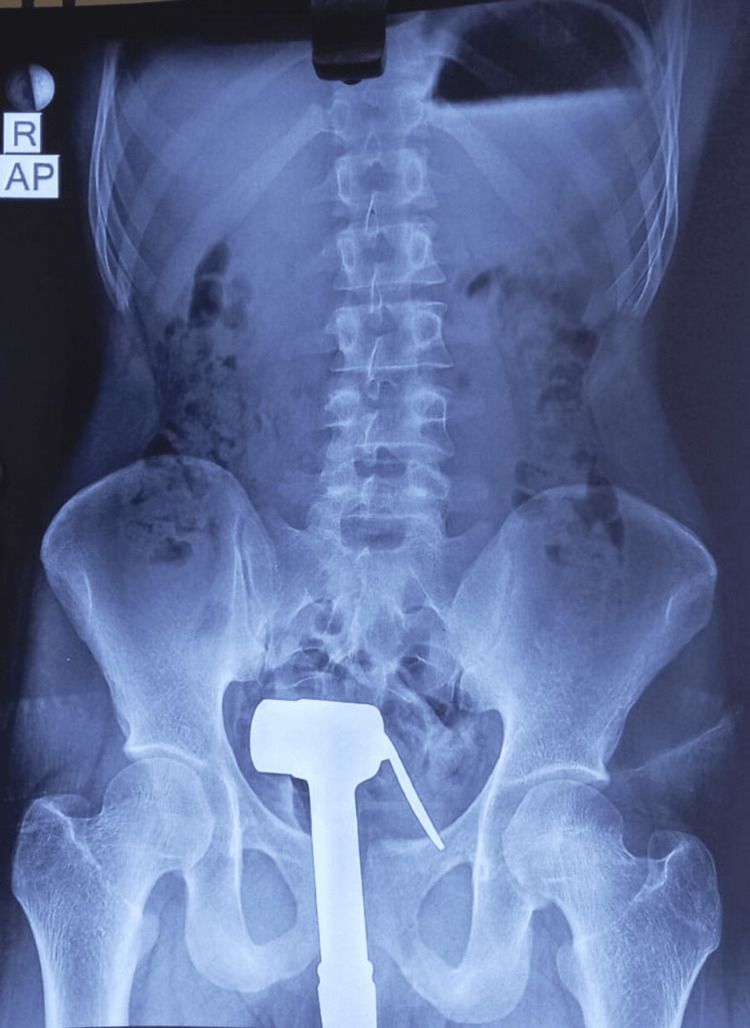

該淋浴器整個進入直腸腔內,僅有部分管線仍留在肛門外。患者整夜等待並嘗試取出未果

,翌日上午甚至請來水電工剪斷外接管線。

在初步評估後,決定於全身麻醉下進行檢查,於直腸內塗抹凝膠進行指診,並逐步擴張肛

門。

手指得以伸入直腸壁與淋浴器把手之間;以兩指按壓把手、拇指穩定其餘部分後,整個淋

浴器得以經肛門完整取出。